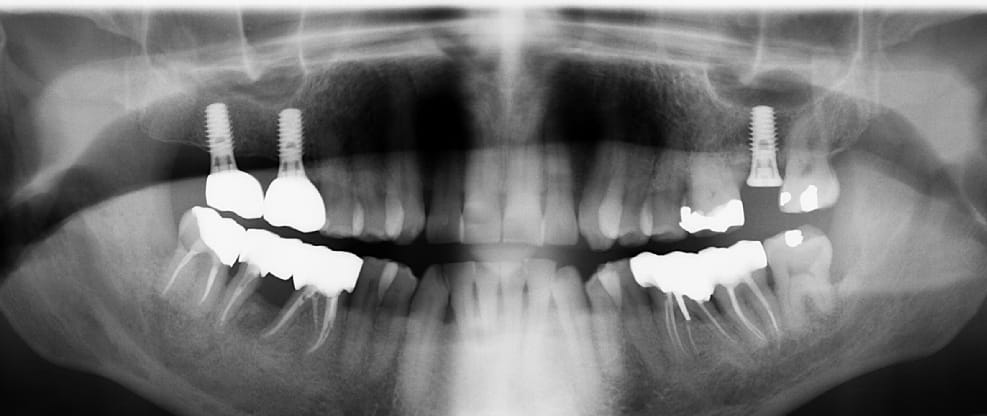

Le temps de poster quelques cas, on en discute après.

Celui-ci, la racine distale de 27 a été amputée en 2012 pour raison paro, la coiffe réalisée immédiatement après sans dépose de la RCR. Elle n'est pas solidarisée à la 26.

La 46 a été réalisée par mon prédécesseur en 20XX, extraite, un bridge a été réalisé entre 45 et 47 l'année dernière.

Bridge cantilever datant de 20 ans (24) 25 26 27, lésion paro entre 26 et 27.

Découpe entre 26 et 27, amputation de la racine distale de 26, et réfection (24) 25 26.

Réalisation de 46 () 47 solidarisées, après extraction de la racine mésiale fracturée de 47; quelqu'un y avait mis un tenon, mais pas dans la distale. C'est du vice, si vous voulez mon avis.

Elles sont bizarre tes radios, on dirait qu'une racine a poussé en 24 entre temps.